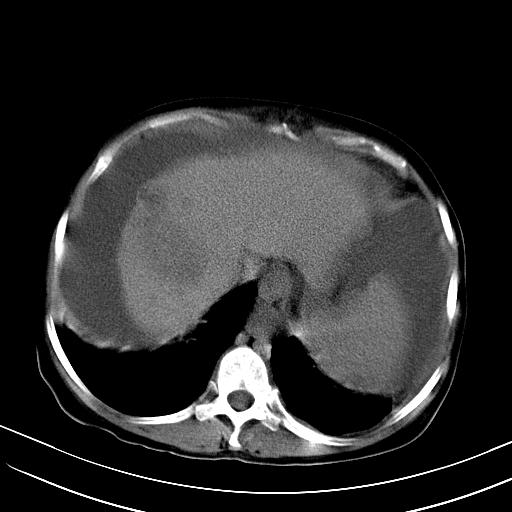

1)肝右叶肝癌并肝动静脉漏。2)肝硬化,腹水。3)胆囊炎。

1)肝右叶肝癌并肝动静脉漏 门v右支瘤栓伴海绵样变。2)肝硬化,脾大 腹水。3)胆囊炎。门v高压.

1)肝右叶肝癌并肝动静脉漏。2)肝硬化,腹水。3)胆囊炎。 4,脾大,脾囊肿

1)肝右叶肝癌,考虑并发肝动静脉漏。扫描时间好像慢了。2)肝硬化,门脉高压、脾大、腹水。